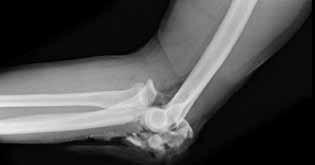

.Figures 11a and 11b show the radiographs of the open fracture of a 46-year-old man who injured his elbow on his nondominant arm in a motorcycle crash. On the day of injury, he underwent irrigation and débridement of the fracture. He was also treated with antibiotics. Which of the following definitive treatment methods will most likely lead to the best functional outcome?